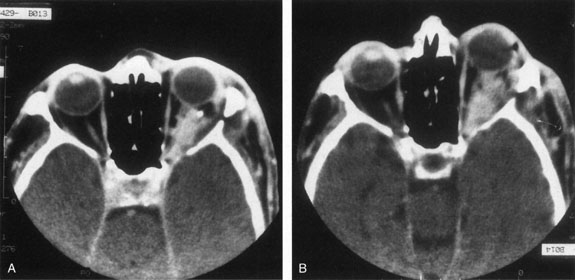

Contrast-enhanced CT of the orbits with direct and coronal cuts is the radiologic study of choice for these patients.45 A well-demarcated, encapsulated oval or rounded mass is revealed, which is typically intraconal in the lateral part of the middle third of the orbit (Fig. 5) but occasionally may extend to the extraconal space.42 Septa within the tumor may be apparent on high-resolution CT. The posterior pole of the globe frequently is indented by the rounded anterior margin of the tumor.42 The optic nerve typically is displaced rather than surrounded by the tumor. Subtle outward bowing of the lateral orbital wall or increase in orbital size may be present, consistent with a long-standing, slowly growing mass lesion.10,42 Enhancement with intravenous contrast occurs and may be homogeneous or inhomogeneous.10,45 Rarely, cavernous hemangiomas may occur as an intraosseous tumor within the orbital or facial bones.42,53–55 Although usually an isolated intraorbital lesion, multiple lesions in one orbit occurred in 8 of 164 (5%) patients of three combined large studies,10,42,45 and bilateral multiple cavernous hemangiomas also have been described.56 In contrast to patients with venous flow malformations in which phleboliths are common, phleboliths are rare in cavernous hemangiomas. Three large studies comprising 164 patients with cavernous hemangioma all reported that no calcification was detected within the tumor.10,42,45If the diagnosis is still unclear or if better definition of details and localization of the lesion is required, then MRI should be performed. Magnetic resonance imaging demonstrates nonspecific characteristics of a lesion isointense to muscle and gray matter on T1-weighted images and hyperintense on T2-weighted images (Fig. 6).57 The lesions show initial central patchy enhancement, which fills up homogeneously within 20 to 60 minutes.58 If ultrasonography is performed, B-scan ultrasonography shows a well-circumscribed mass with a sharply defined anterior acoustic border.23 A-scan ultrasonography shows high reflectivity of the echo signals resulting from the multiple blood-filled vascular channels, regular internal structure with a higher anterior and posterior spike marking the capsule, and moderate sound attenuation (angle of decrease of the echo spike within the lesion).24 Arteriography is not indicated.

Fig. 6. Cavernous hemangioma. Axial magnetic resonance imaging demonstrates a well-defined, homogeneous intraconal mass that is isointense to muscle and gray matter on T1-weighted image (A), and hyperintense on T2-weighted image (B). Note the displacement of the optic nerve and indented posterior globe.